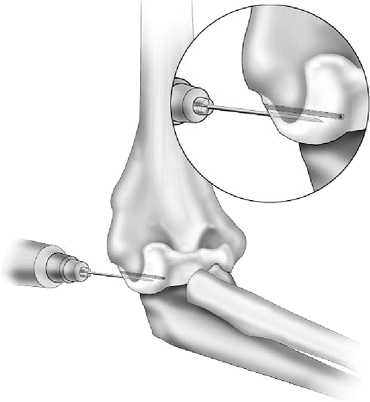

If reconstructed, the graft is usually positioned first and then

secured at the conclusion of the anconeus reconstructive procedure. Two

drill holes are placed from posterior to anterior through the

midportion of the capitellum approximately 5 to 7 mm apart (Fig. 23-8), and the anconeus is brought under the intact or reconstructed lateral ulnar collateral ligament (Fig. 23-9).

Figure 23-8. Two drill holes 5 to 7 mm apart are placed through the center of the capitellum.

|